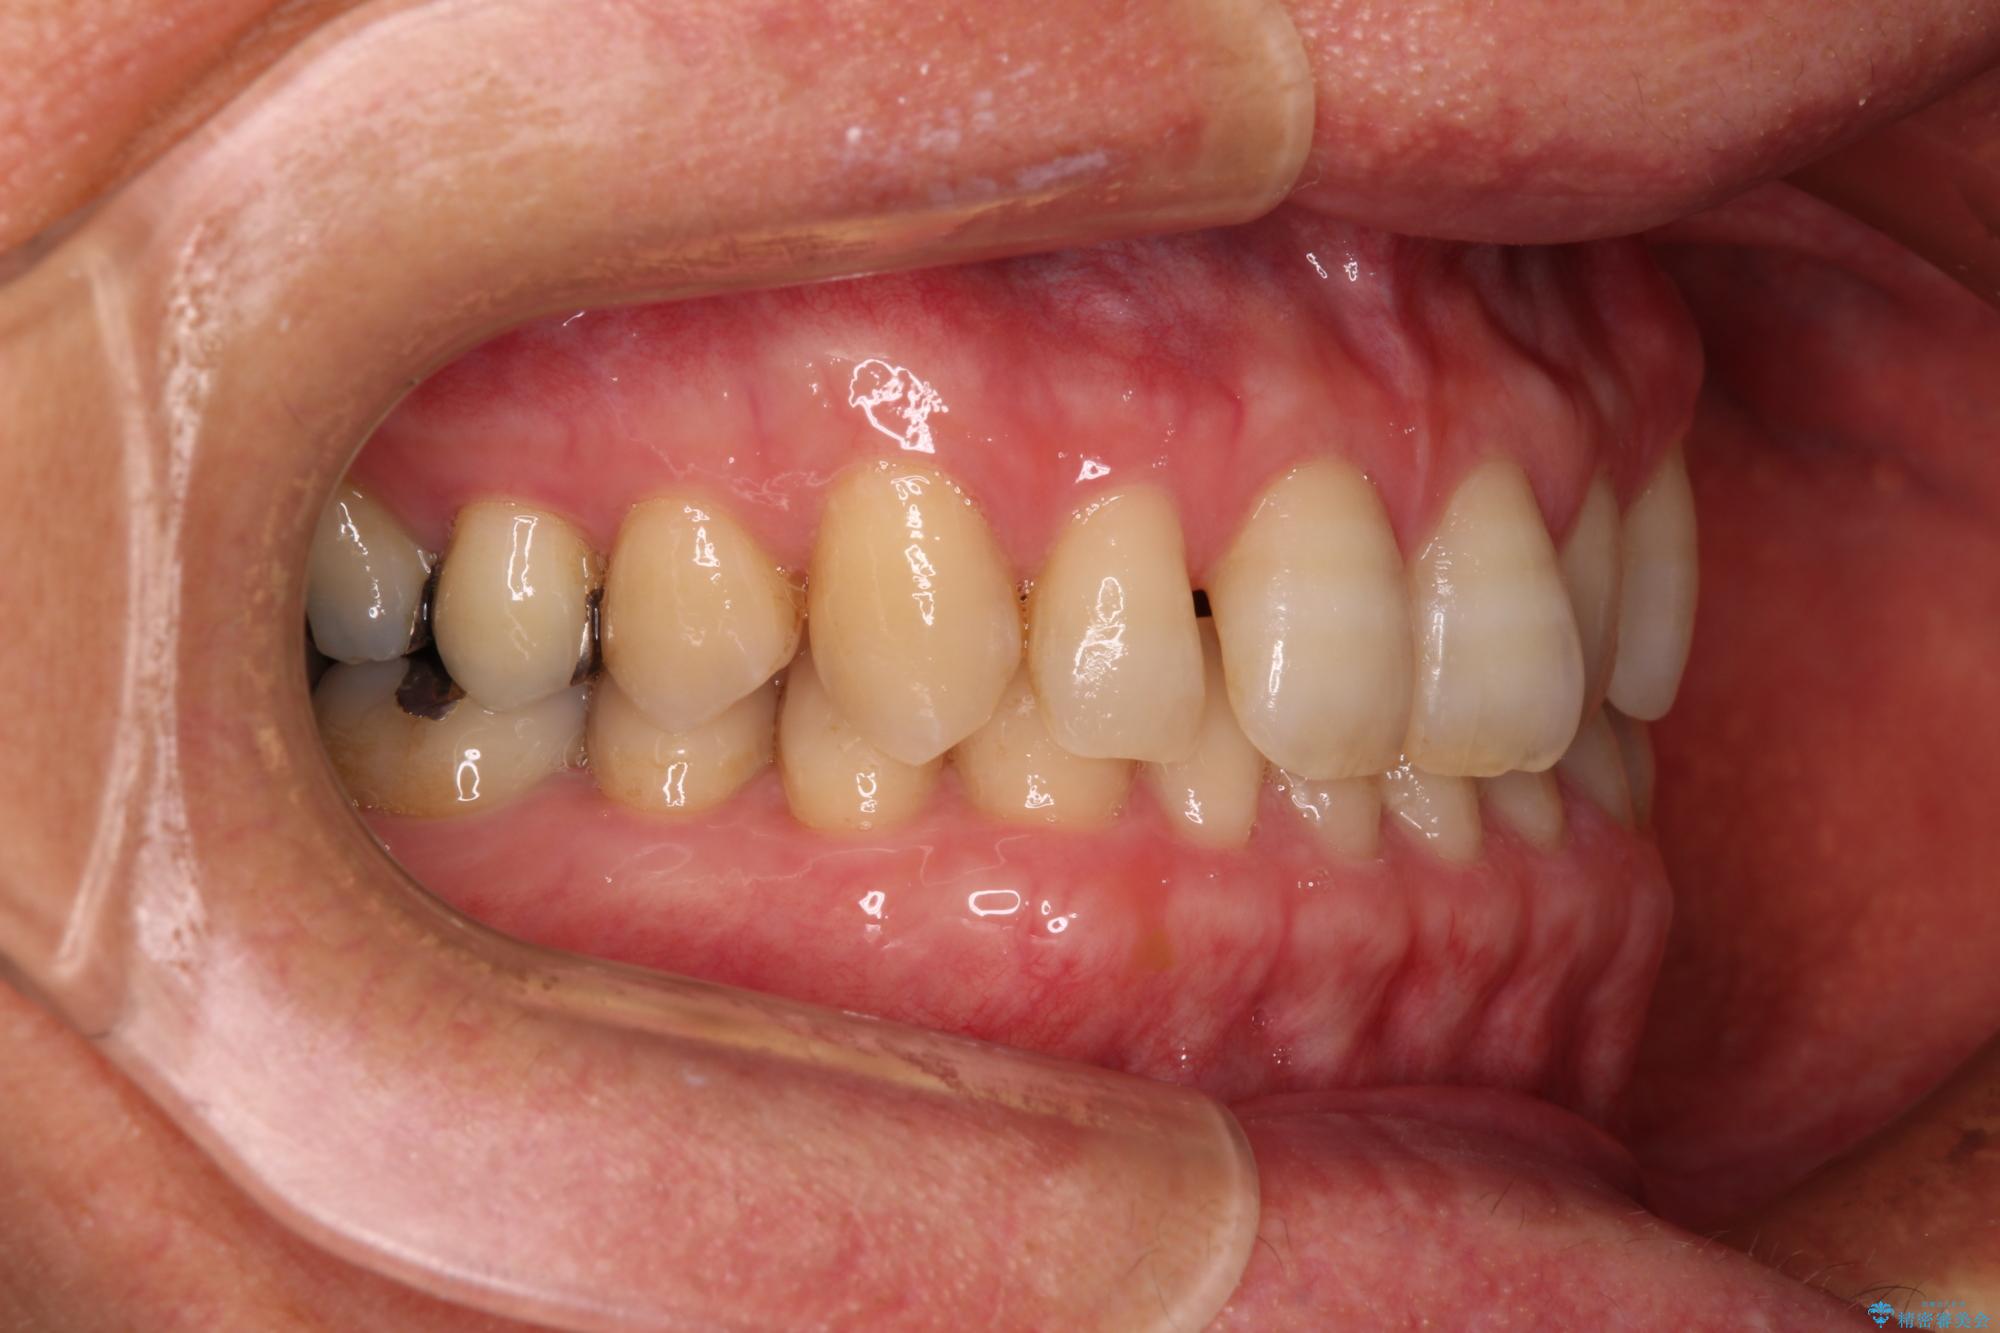

- 前歯のデコボコと隙間の空いた歯列を気にして来院された患者様です。

下顎前歯が隠れるほどのディープバイトにより、強い咬合力と突き上げで上顎歯列に隙間が空いている状態でした。

手前に傾斜している奥歯をワイヤー装置で立ち上がらせ、咬み合わせの高さを挙上することで突き上げを解消し、空隙歯列を改善していくこととしました。